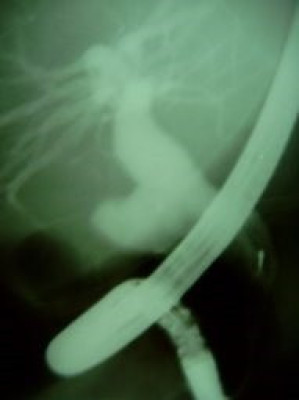

Quiste de coledoco tipo II

Envíado por Dr. Carlos Miguel Zavaleta Consuegra